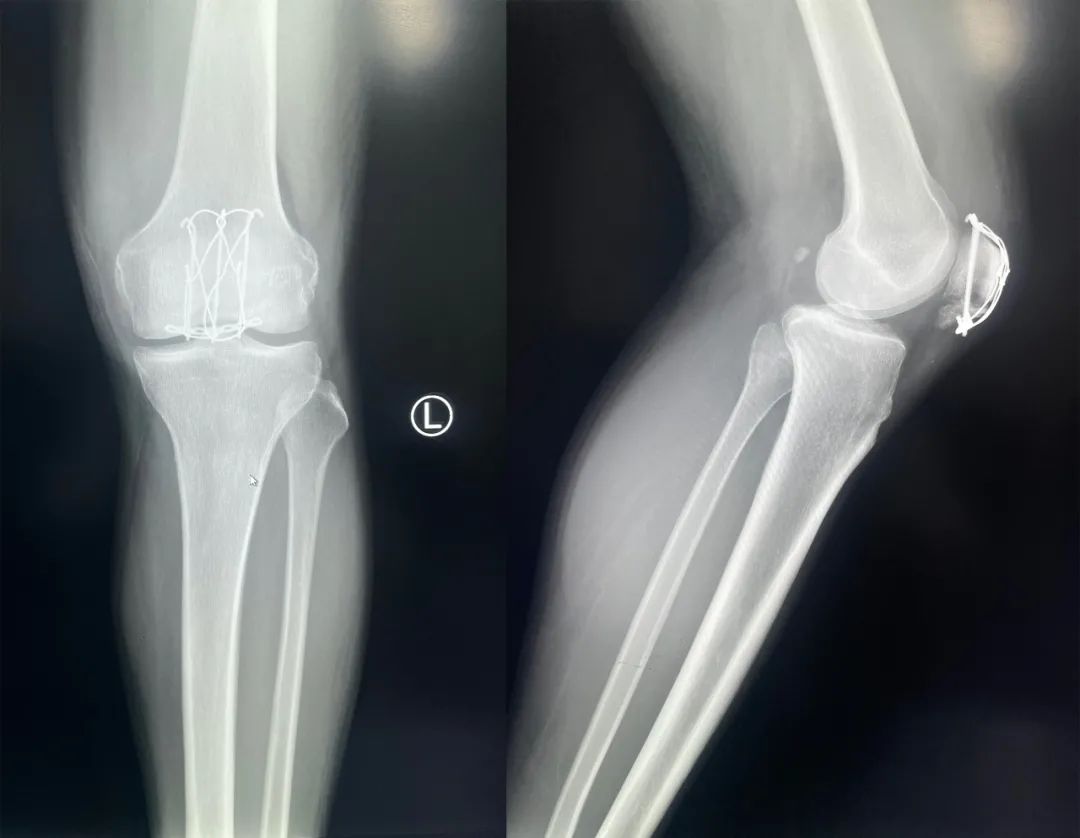

髌骨骨折正侧位  图源:作者提供

除以主诉和典型体征外,膝关节 X 线片也是必不可少的一项辅助检查,以膝关节正侧位 X 线片最常见,如果怀疑纵向骨折,膝关节屈曲 45° 时髌骨 30° 切位片可以辅助诊断。

完全关节内骨折克氏针加张力带固定  图源:作者提供

克氏针加张力带钢丝;有第三个骨折块则采用拉力螺钉或克氏针加张力带钢丝固定;对于 4 个或 4 个以上的骨折块采用克氏针加螺钉加张力带钢丝进行固定;对于严重粉碎和软骨面广泛破坏的髌骨骨折,髌骨部分或完全切除也是一种可行的办法。